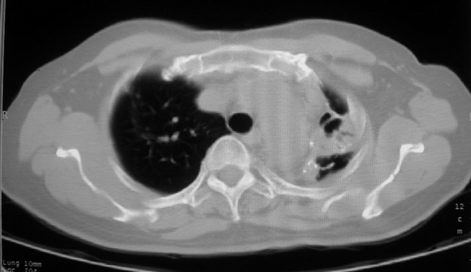

以下是引用李衡钧在2008-7-24 14:24:00的发言:[br]左侧胸廓变小,左肺上叶见大面积致密阴影,其内有空洞及不规则钙化。上纵隔略向左移位,上肺胸膜增厚。左肺门及纵隔淋巴结增大。右肺见散在的致密结节影。[br]印象:继发性肺结核。